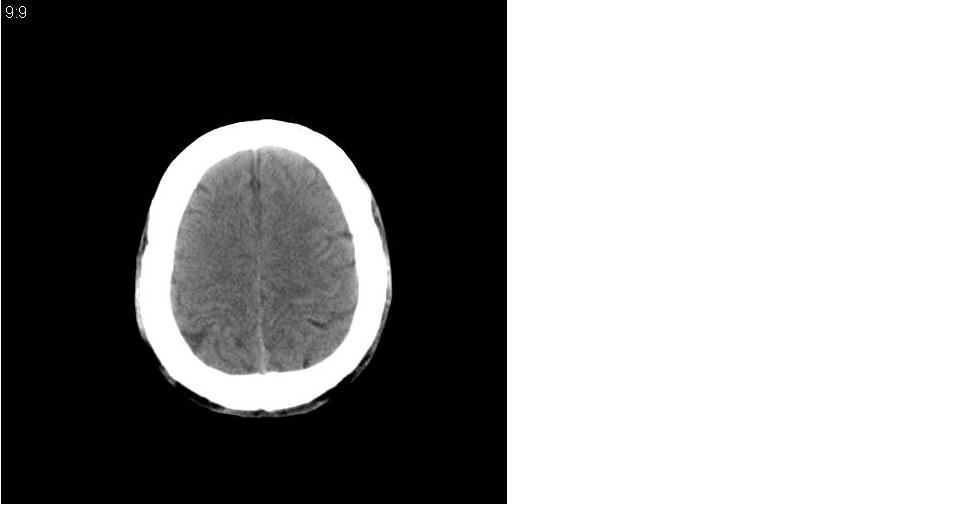

男 32岁,外伤。

大枕大池、蛛网膜囊肿